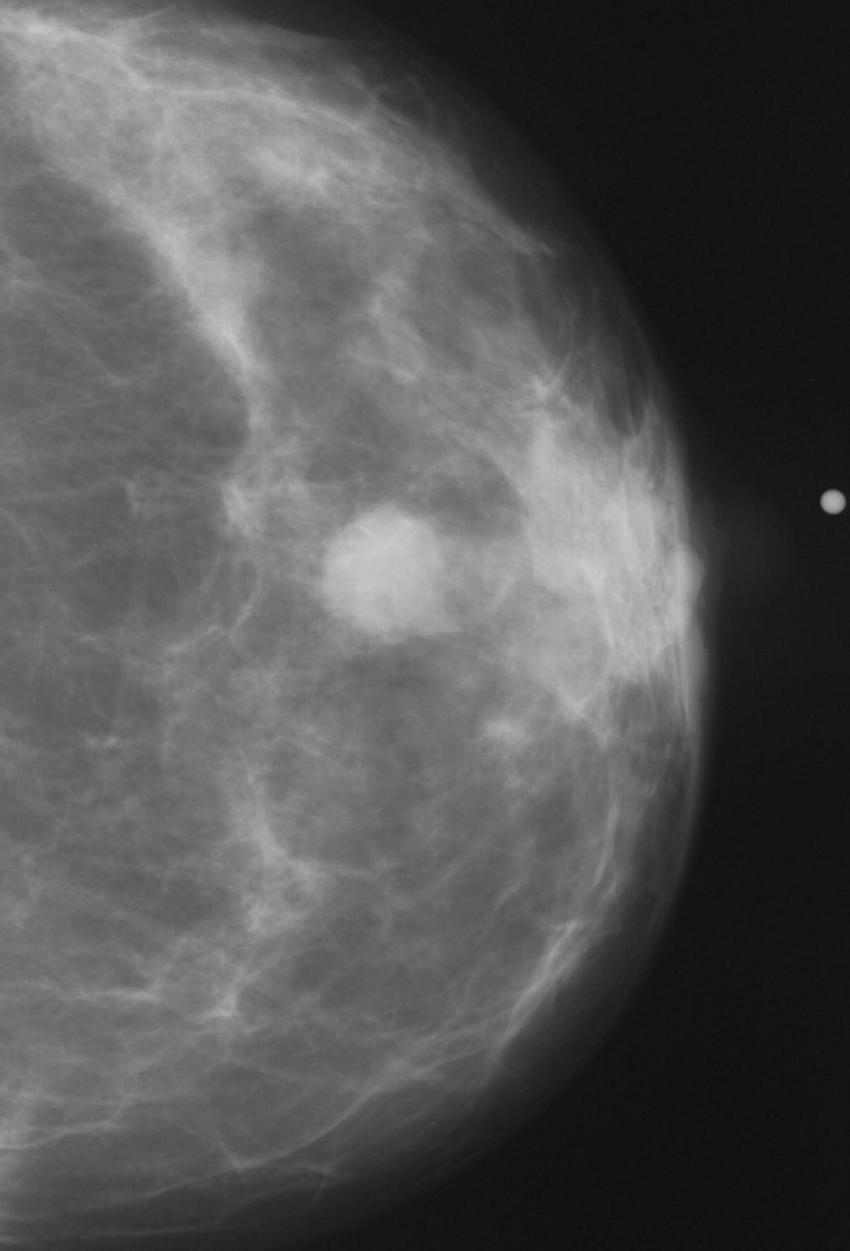

Figure 3. Normal mammogram.

High-res (TIF) version